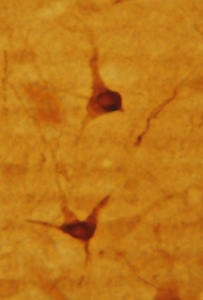

HC image of neurons staining for 5-H1AA in the raphe nucleus of the rat brainstem. The tissue was fixed with 4% formaldehyde in phosphate buffer, before being removed and prepared for vibratome sectioning.